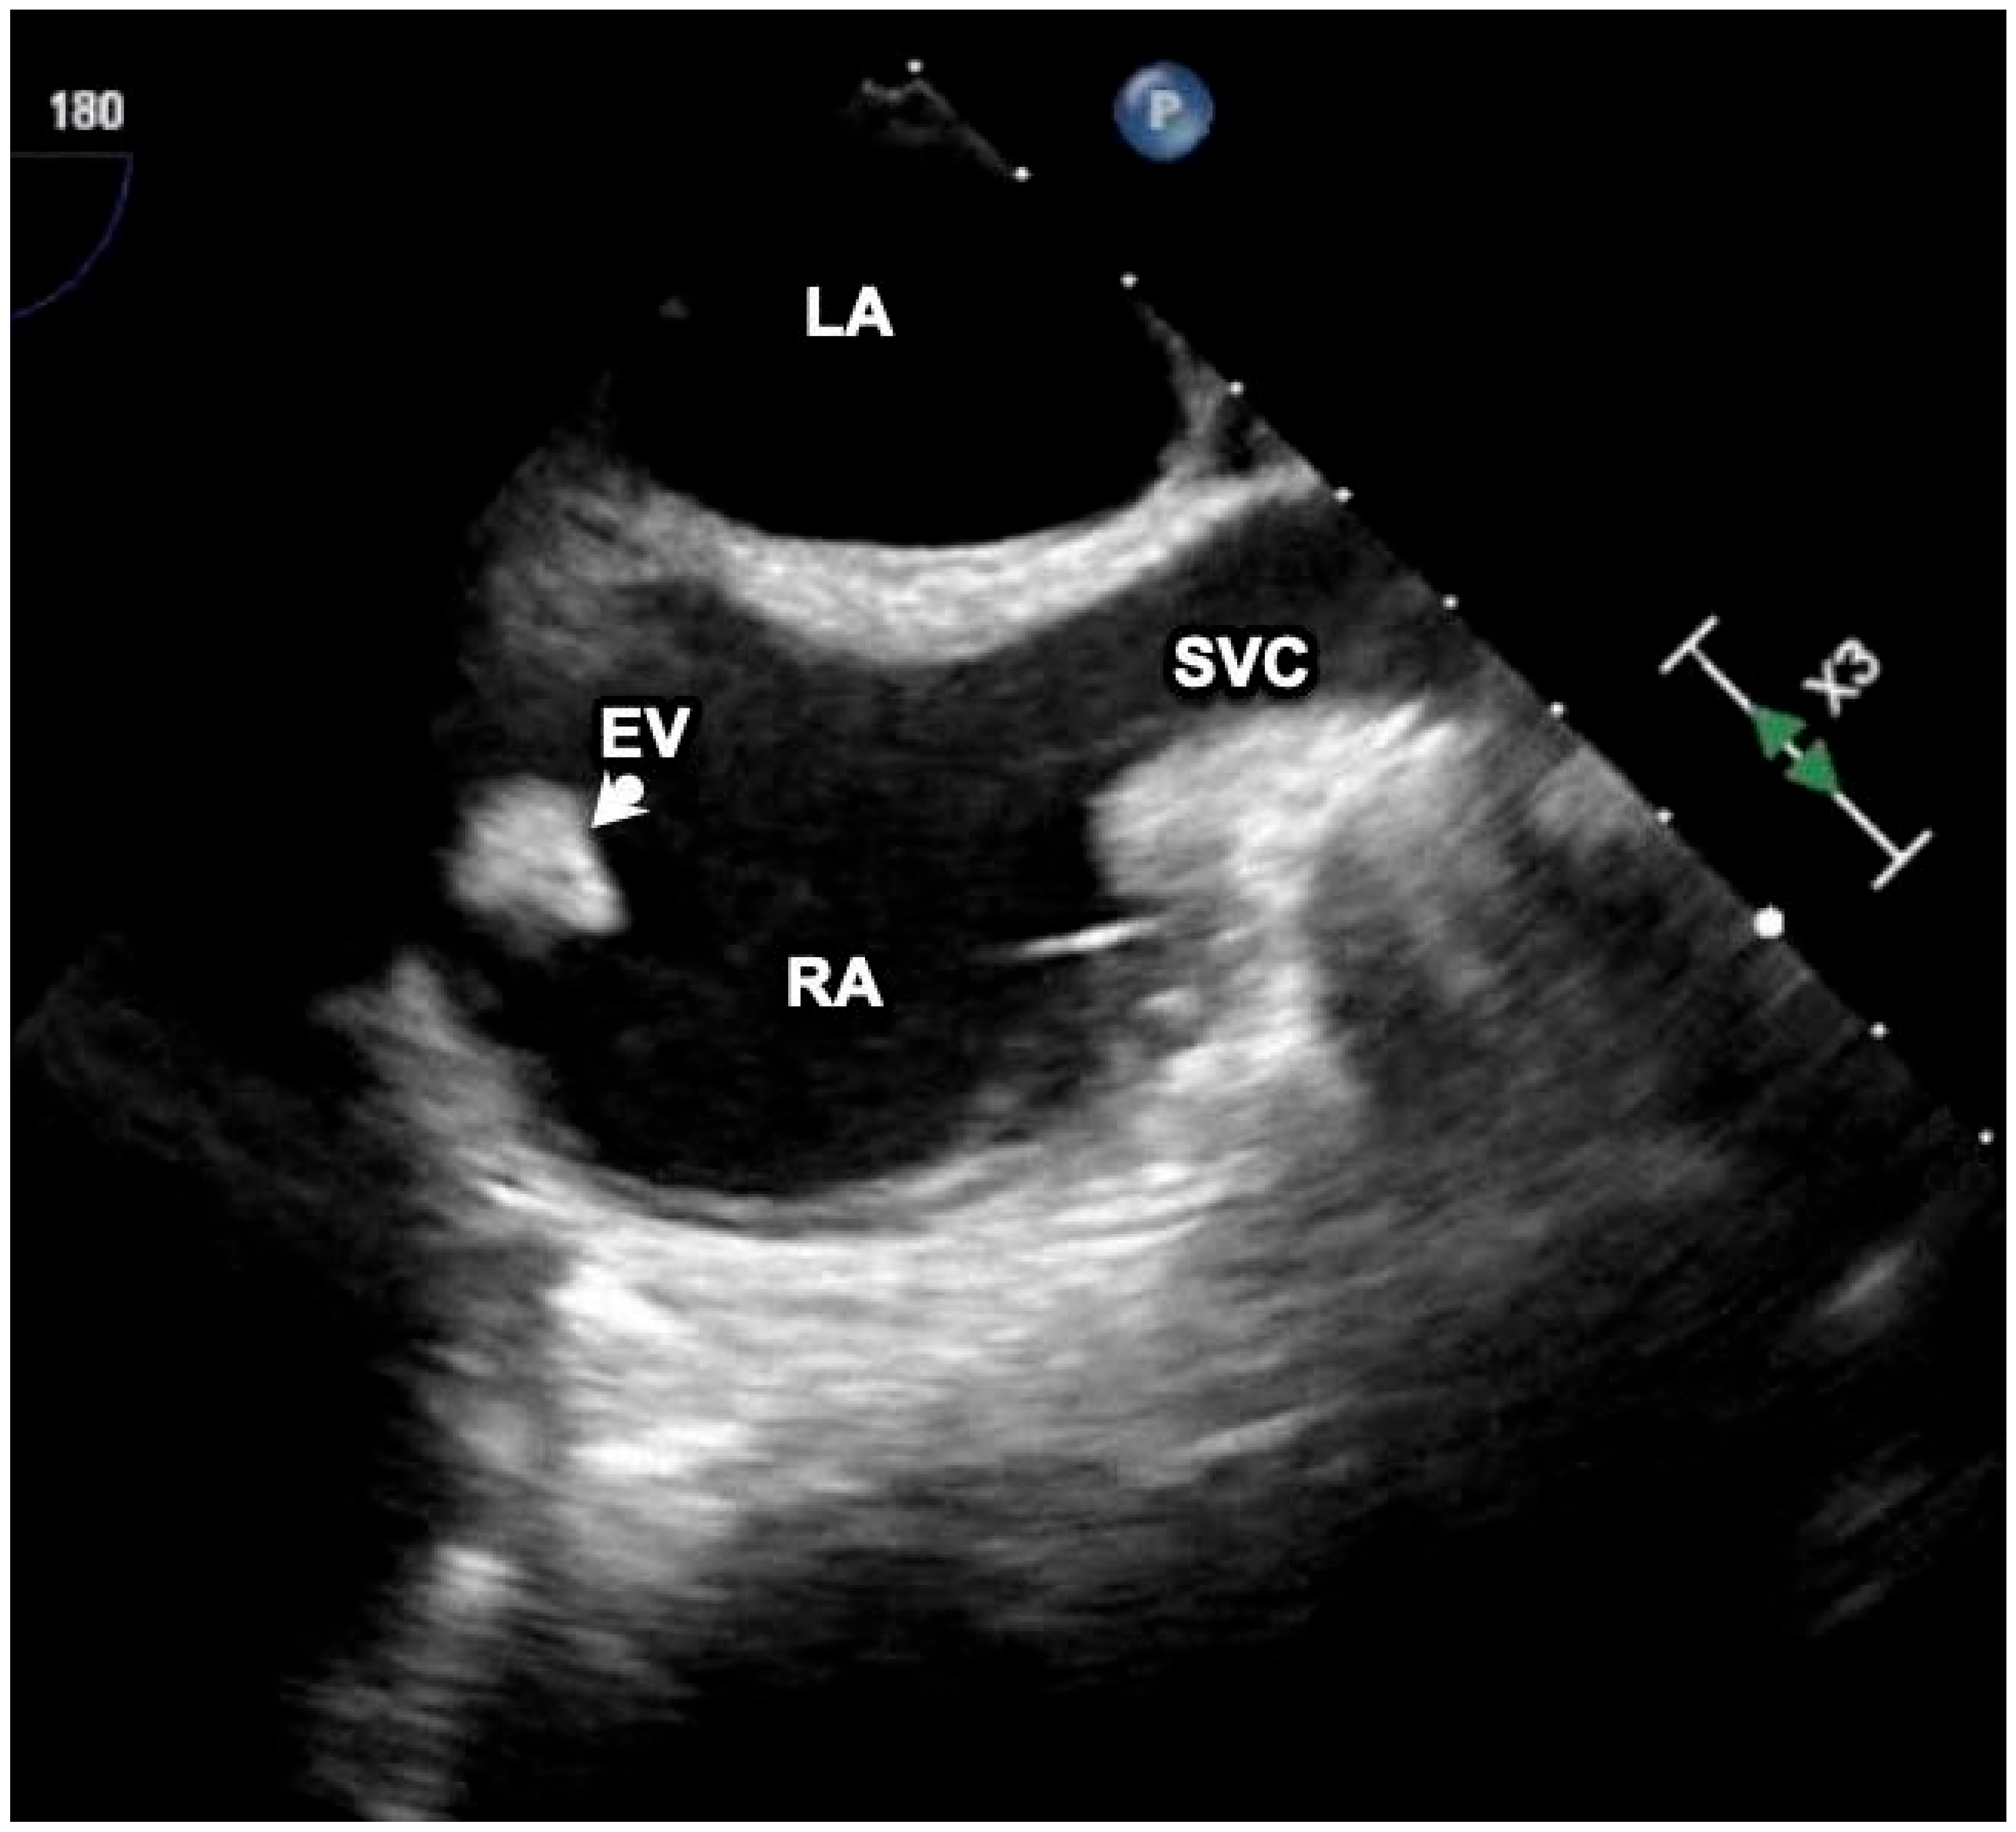

A Case Report of Eustachian Valve Endocarditis Due to Salmonella typhimurium in an Aids Patient

Case Report